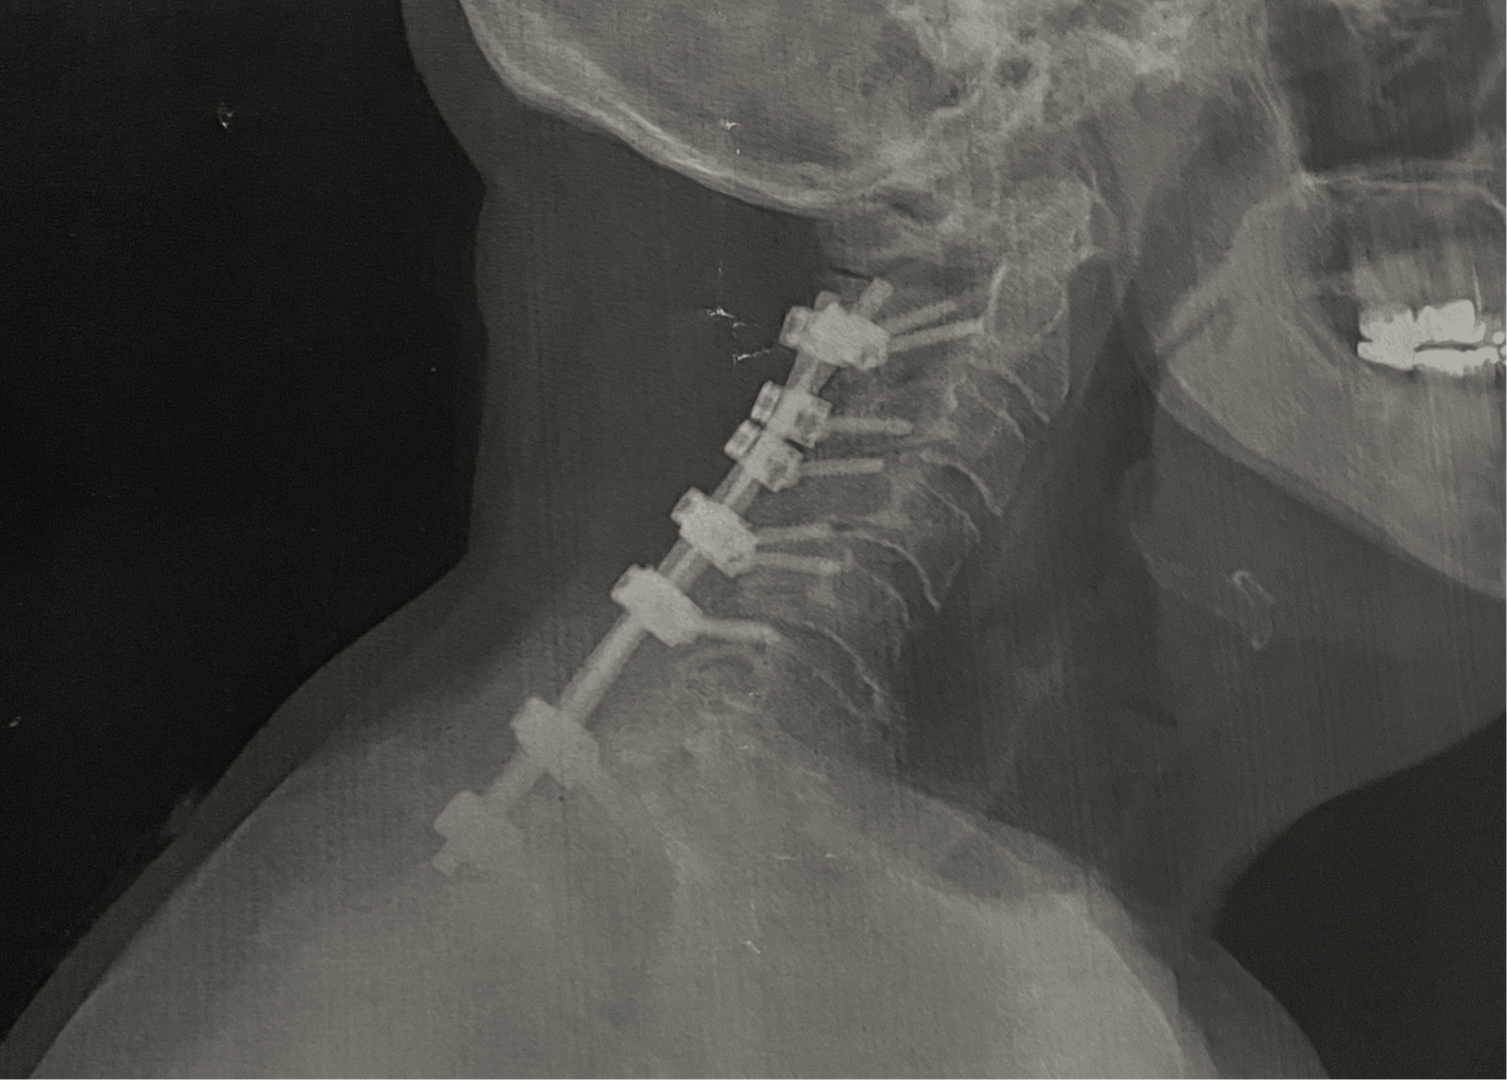

When I was faced with having a very radical spine surgery, I thought my theatre days, as I knew them, were over. In December 2023 I had a six level (C2 to T2) spinal fusion. My spine was crumbling from degenerative disc disease, and spinal stenosis. My surgeon reinforced my spine with two 12” titanium rods and fourteen screws. I was told I may never walk again; but I’m walking! I have permanent nerve damage in both feet and both hands.